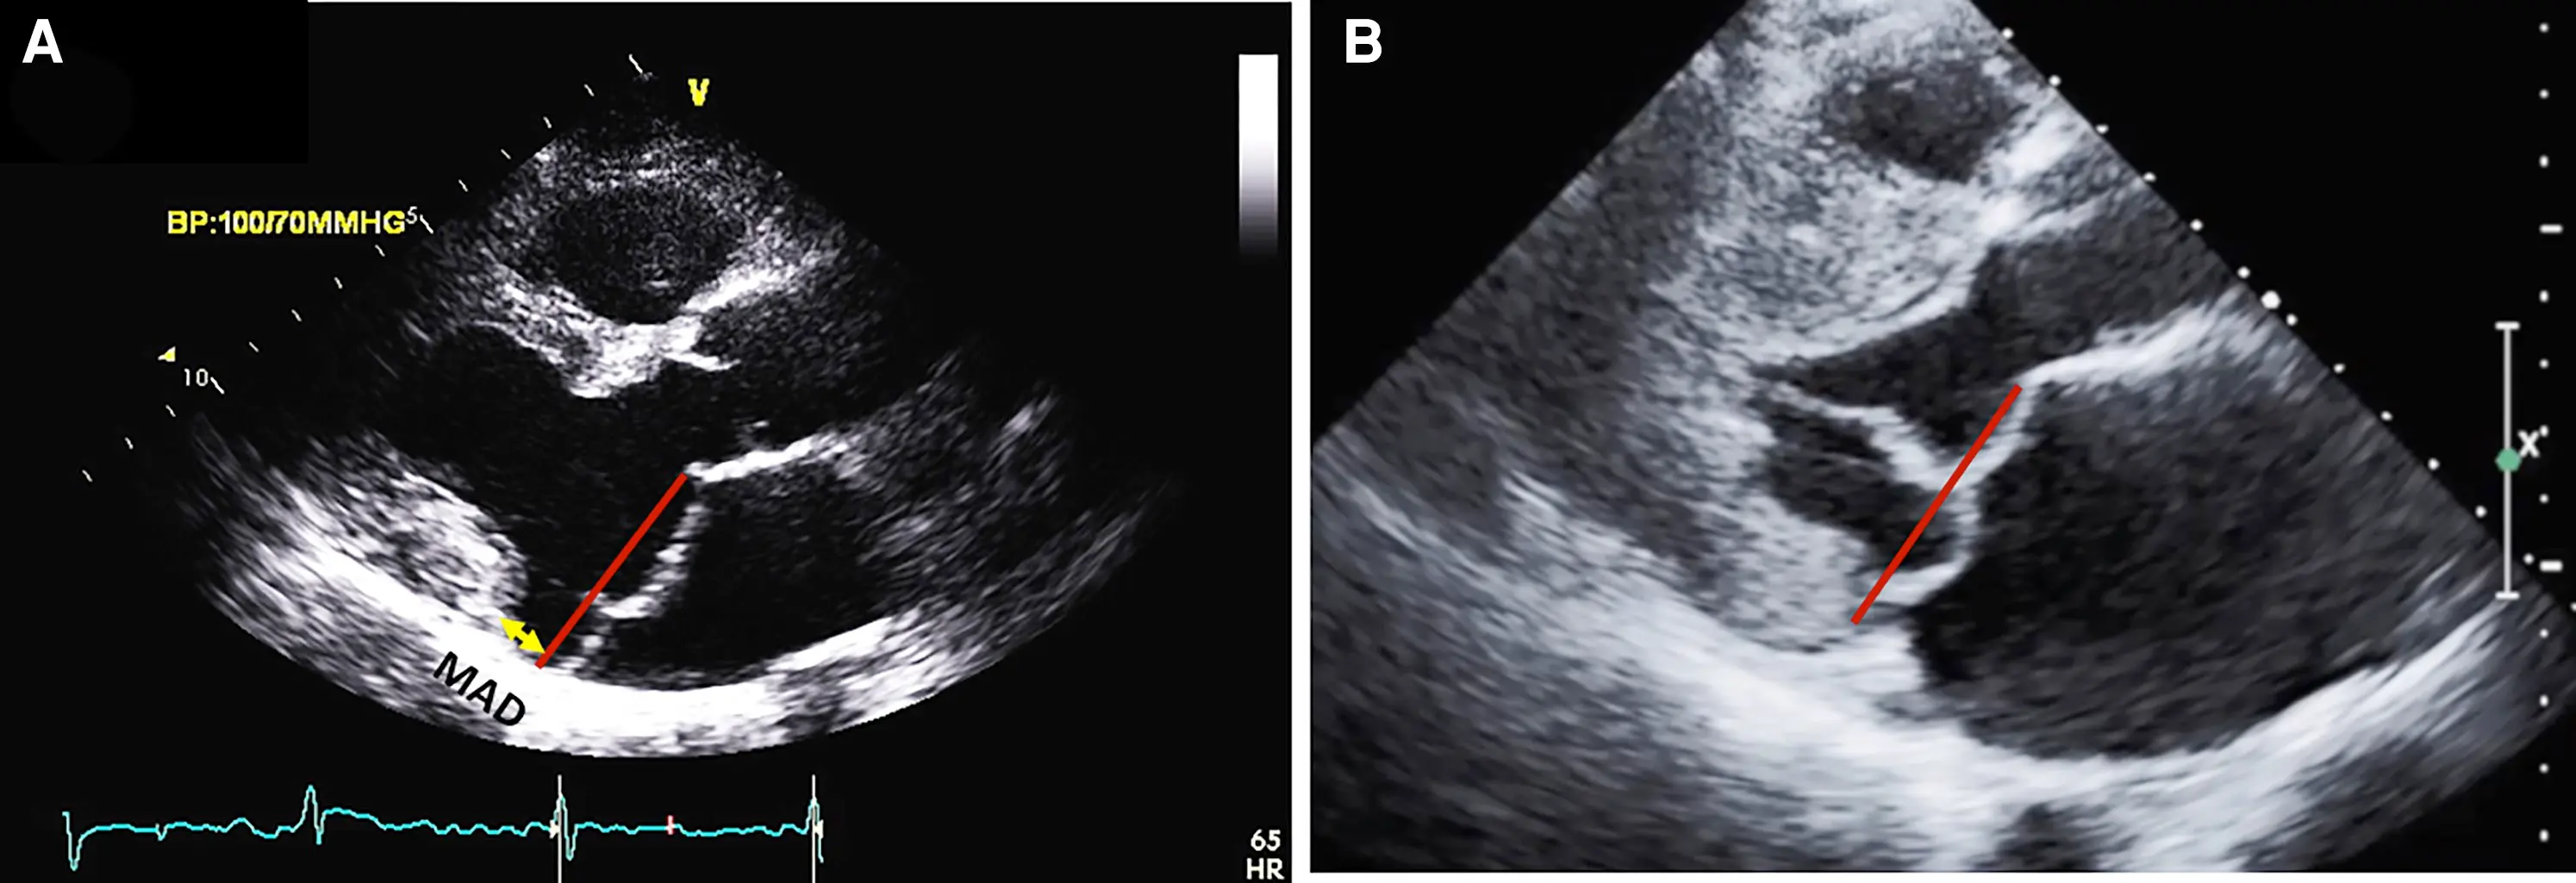

• MAD length is measured in the parasternal long axis view (or equivalent sagittal views on CMR), from the insertion of the posterior leaflet on the detached mitral annulus to the border of the bulging LV myocardium.

Figure source: 1. CMR long-axis view in end-systole displaying mitral valve prolapse with MAD (yellow arrow). The red line indicates the plane of the mitral annulus.

• The upper limit of MAD is defined at the level of posterior leaflet insertion on the annulus/left-atrial-wall, whereas the lower limit is defined at the level of the LV myocardium

• The ventricular myocardium, having lost its basal attachment, bulges more apically than normal, forming the apical margin of the MAD trench